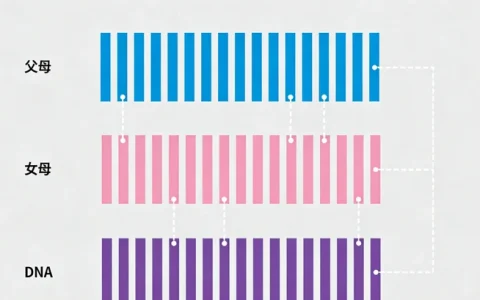

传统微生物培养是诊断的金标准,但存在周期长、阳性率低的局限。非结核分枝杆菌基因检测,是一种基于分子生物学原理的精准诊断技术。该技术直接针对病原体的特定基因片段进行检测和分析,能够快速、准确地鉴定出致病菌的具体种类。

其核心优势在于,不仅能确认是否为非结核分枝杆菌感染,还能进一步分型,确定到底是哪一种具体的菌种在“作祟”。这种精确到种的鉴定能力至关重要,因为不同菌种的致病性、药物敏感性差异巨大,直接决定了后续治疗方案的有效与否。